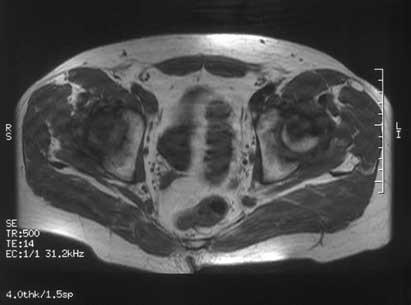

RESONANCIA MAGNETICA  muy sensible a los cambios isquémicos tanto en zonas epifisarias como en zonas metafisodiafisarias.  diagnóstico precoz: 2-5 días.  El patrón de imagen puede variar según el grado de afectación y la respuesta individual.  Una doble linea entre el hueso isquemico y no isquemico.  correlación entre las imágenes de RMN y los hallazgos histopatológicos  Visualiza la integridad del cartílago articular y permite identificar cuerpos libres intraarticulares.

RESONANCIA MAGNETICA